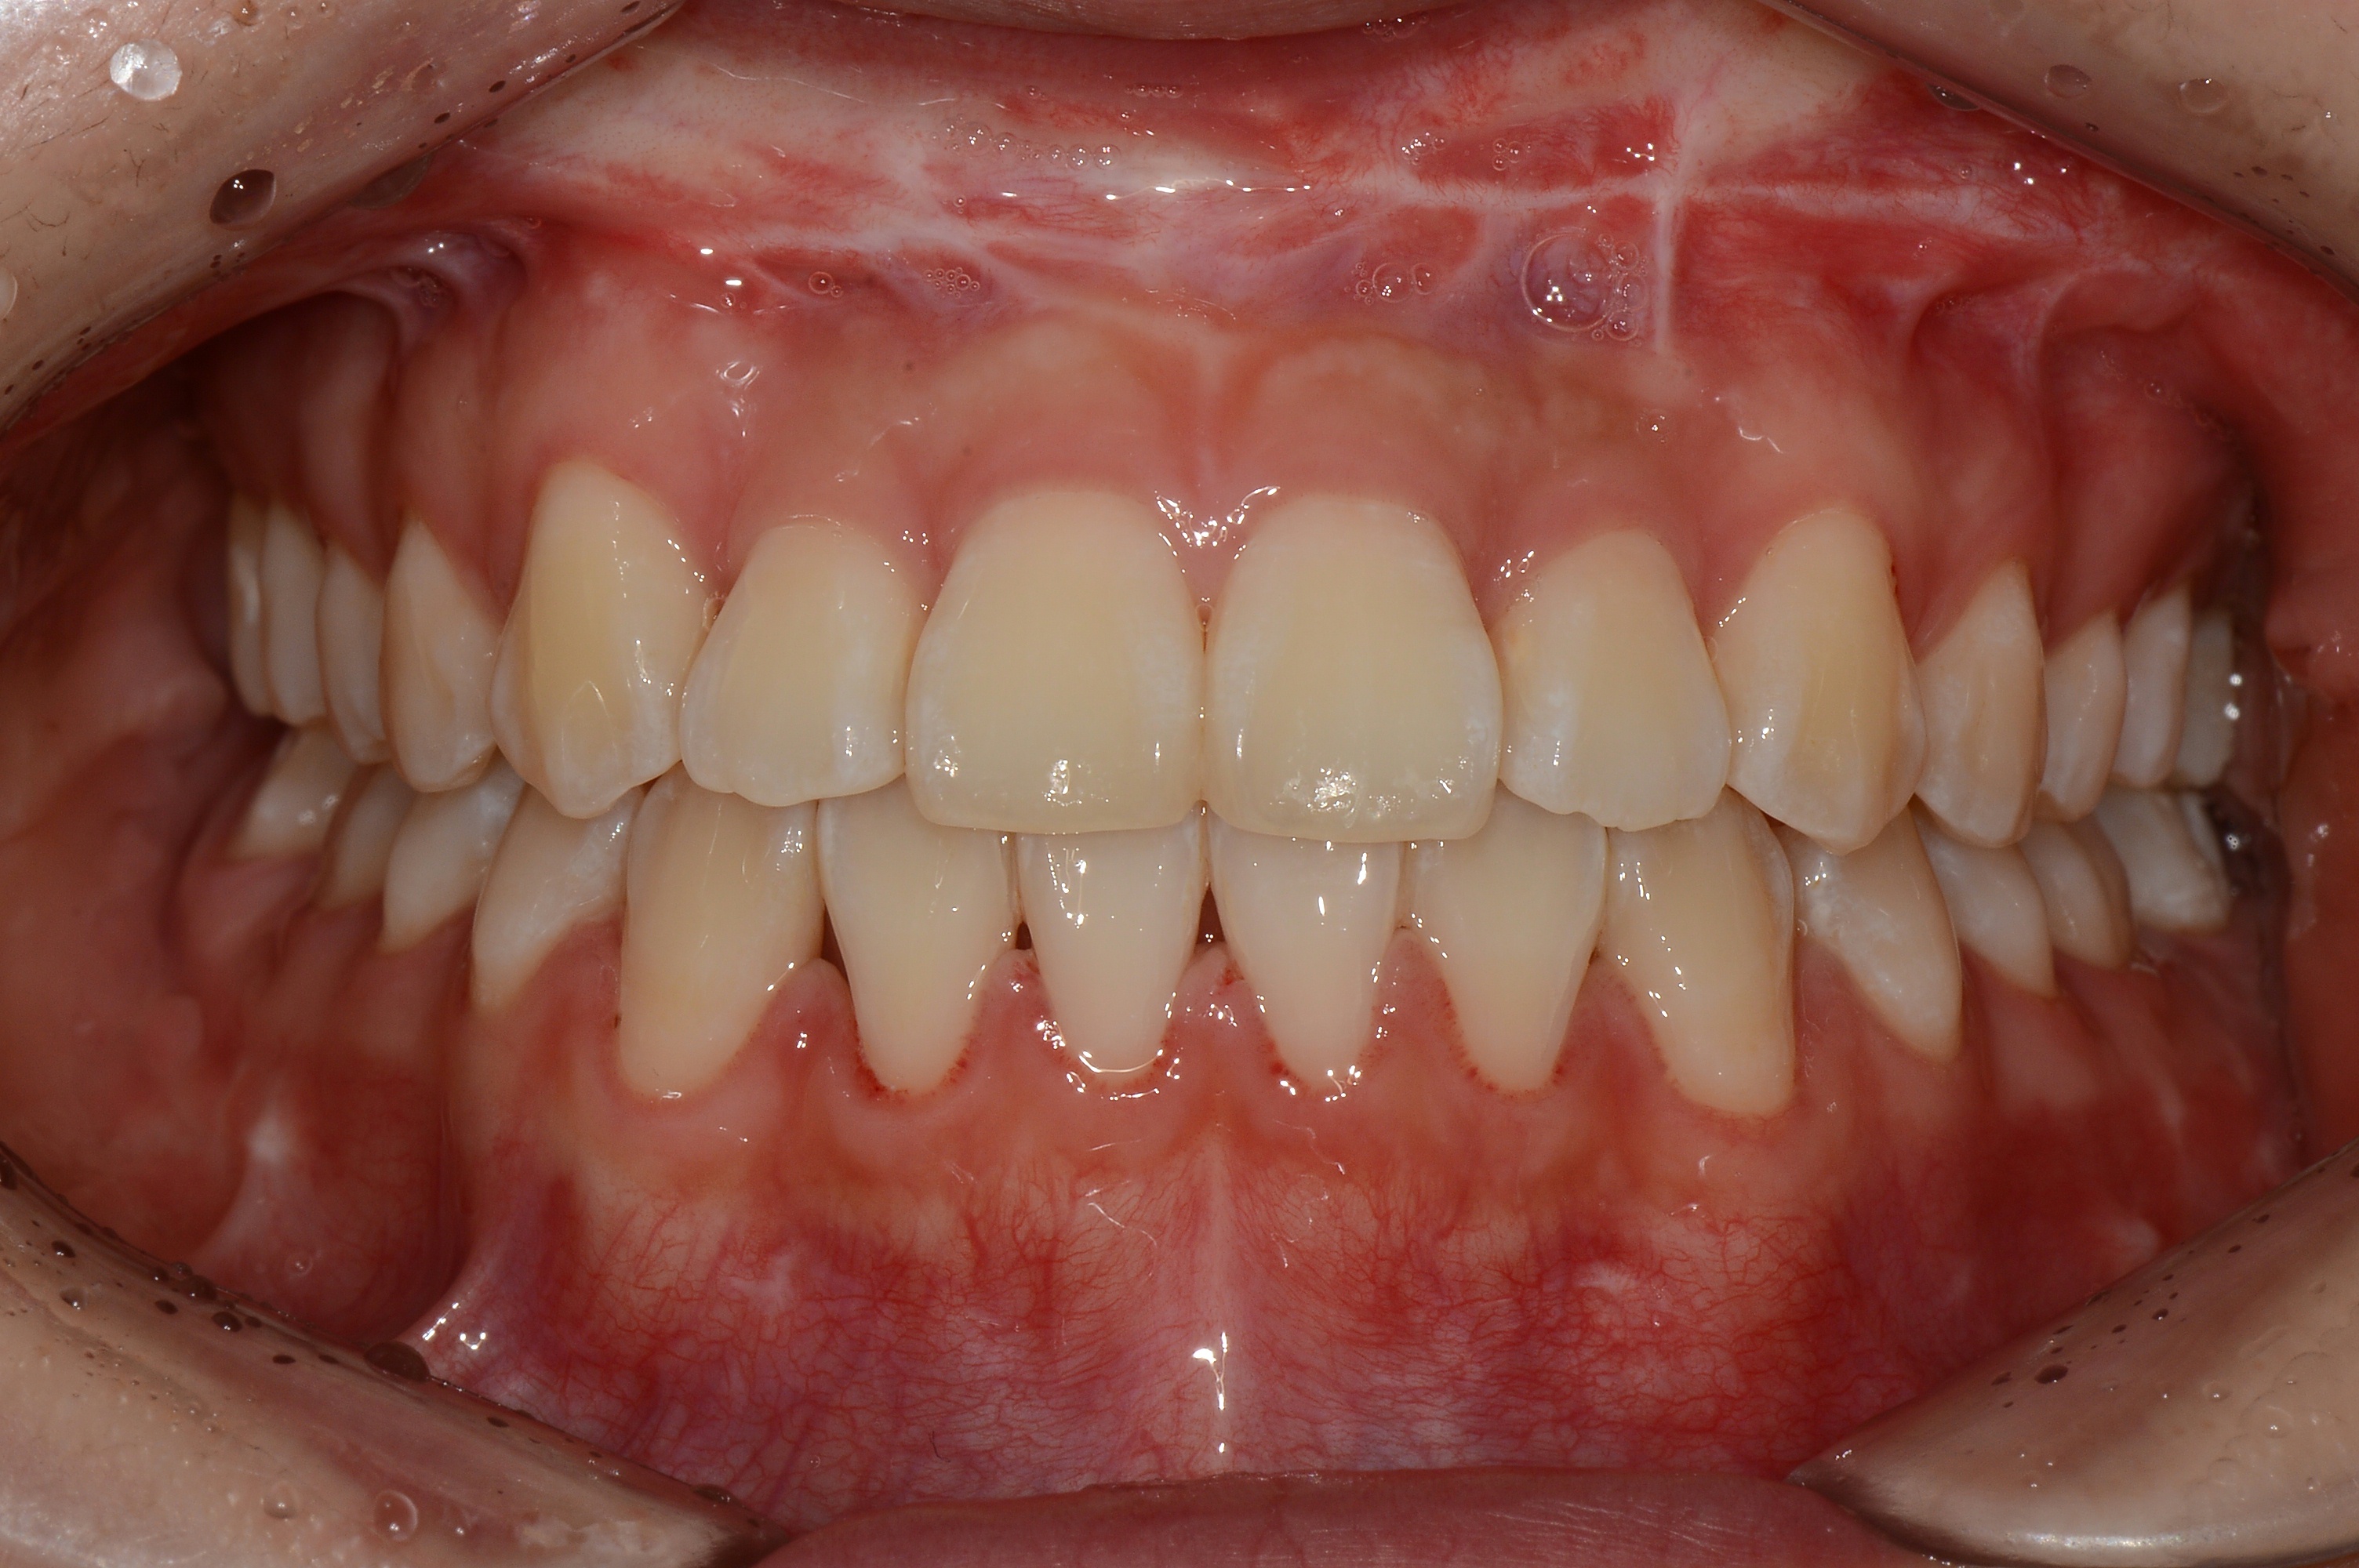

치료 전 사진입니다.